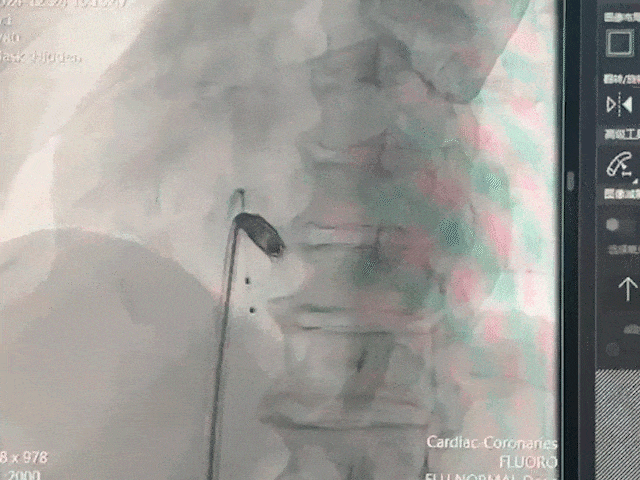

手术过程部分展示

猪尾造影,明确右室心尖、前室间沟、后室间沟、三尖瓣相对位置